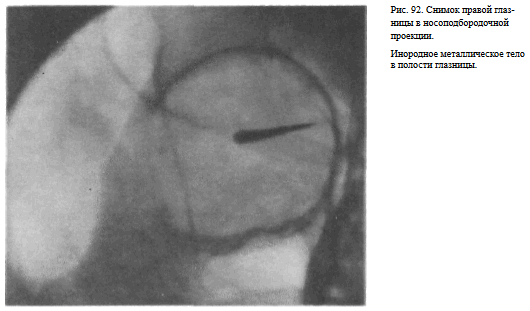

На прицельном снимке каждой из глазниц в этой же проекции, как правило, небольшие изменения структуры стенок, а также мелкие инородные тела глаза видны лучше. Такие снимки широко используют в офтальмологической практике (рис. 92).

Назначение снимка — изучение контуров костей, образующих вход в глазницу, структуры верхней и наружной ее стенок, ширины и контуров верхних глазничных щелей, а также выявление инородных тел в полости глазницы.

В качестве примера информативности снимка глазниц в носолобной проекции для выявления инородных тел глаза и деструктивных изменений стенок приводим два наблюдения.

Одно из них — случай ранения глаза металлической стружкой (рис. 93), другое — случай деструкции верхненаружного края глазницы при доброкачественной опухоли слезной железы (рис. 94).